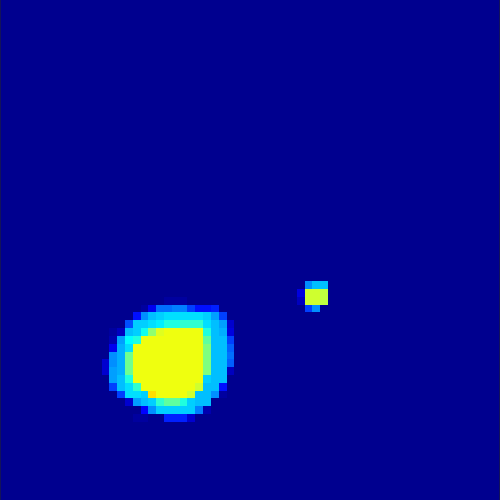

5.2 Monte Carlo Simulation

In order to test the behaviour of the proposed method in a more realistic, random-based test case, we performed a Monte Carlo simulation for dynamic SPECT imaging. First, we created a simple image phantom consisting of an outer and two inner circles which represents the structure of the region of interest (see figure 8(a)). Within those regions we assumed concentration curves over a time period of 90 time steps as displayed in figure 8(b). Based on the tracer intensity in an image frame at each time step, we created a variable number of random decay events (where the number is proportional to the average concentration in one pixel in the whole image frame per time step) with a probability proportional to the concentration in every subregion. They are detected by a virtual double head gamma camera rotating around the patient by 46 degrees per time step, which consists of 374 detector bins. Every simulated decay event is projected onto the scanner and counted by the corresponding detector bin.

In two different tests we fixed the number of events counted by the detector equal to (resp. ) times the average concentration in one pixel. The resulting sinogram images of the accumulated counts in each bin are shown in figure 9.

Based on the sinogram data we applied the proposed algorithm in order to reconstruct the original image sequence. The results for both test cases are shown in figure 10.

As one can see, the method is able to reconstruct the regions properly, even in case of a low count number. Within a number of iterations (average of 100 outer and 10000 inner iterations), the algorithm presents a reasonable reconstruction of the region of interest and the corresponding regional tracer concentration curves. Here, the parameters were not optimized as in the case of the synthesized data sets in the previous section, but kept fixed as , and . With futher optimized parameter values one could possibly provide even better results.